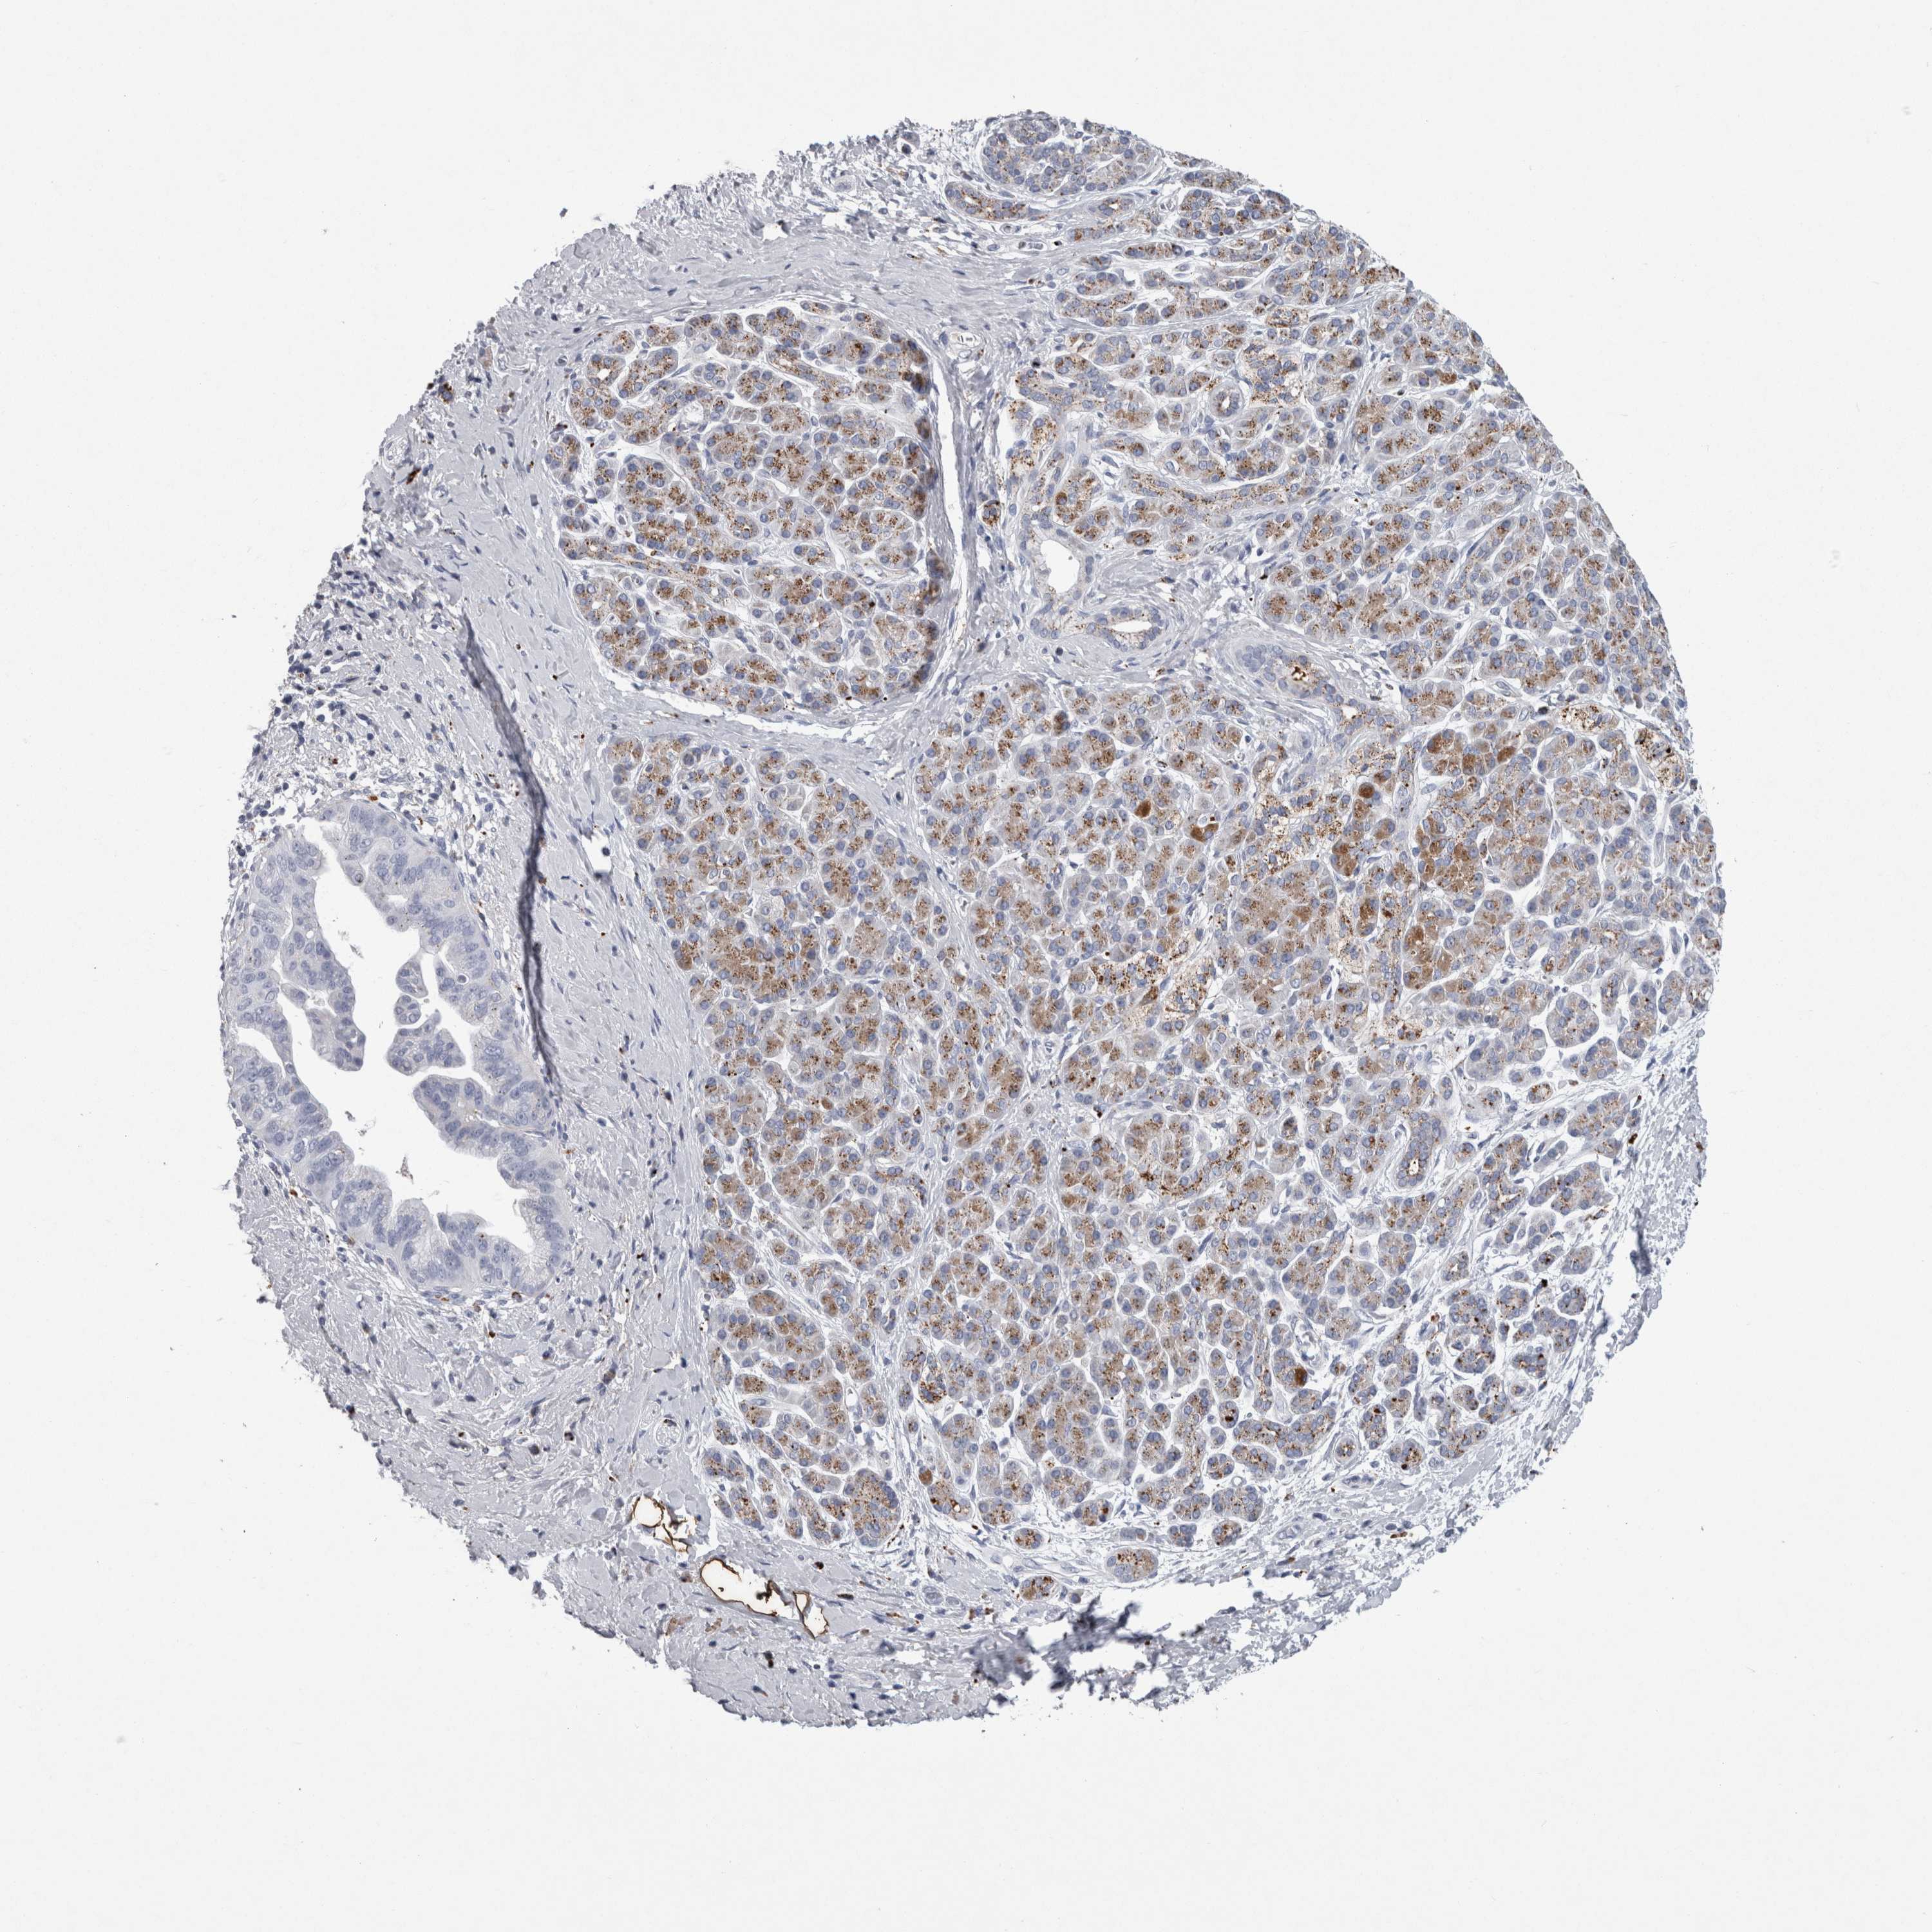

PANCREATIC CANCER - Protein expressioni

A mouse-over function shows sample information and annotation data. Click on an image to view it in a full screen mode. Samples can be filtered based on level of antibody staining by selecting one or several of the following categories: high, medium, low and not detected. The assay and annotation is described here.

Note that samples used for immunohistochemistry by the Human Protein Atlas do not correspond to samples in the TCGA dataset.

Antibody stainingi

Antibody staining in the annotated cell types in the current human tissue is reported as not detected, low, medium, or high, based on conventional immunohistochemistry profiling in selected tissues. This score is based on the combination of the staining intensity and fraction of stained cells.

Each image is clickable and will lead to virtual microscopy that enables deeper exploration of all samples and also displays staining intensity scores, fraction scores and subcellular localization as well as patient and tissue information for each sample.

Antibody HPA021282

Antibody CAB025541

Staining

High

Medium

Low

Not detected

Intensity

Strong

Moderate

Weak

Negative

Quantity

>75%

75%-25%

<25%

None

Location

Nuclear

Cytoplasmic/membranous

Cytoplasmic/membranous,nuclear

Adenocarcinoma, NOS